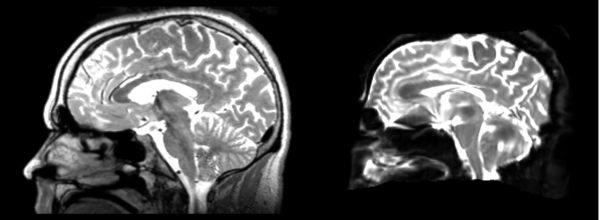

- 53-t2 -> 31-t1 = aff1

- aff1 -> 53-t2 = aff2

The image shows these side by side. The are nearly the same except for the loss of fine detail.

Linear

- 53-t2 -> 31-t1 = lin1

- lin1 -> 53-t2 = lin2

The image shows lin2 and 53-t2 side by side. The image shows there appears to be some change beyond loss of detail, possibly a L-R shift in the front.